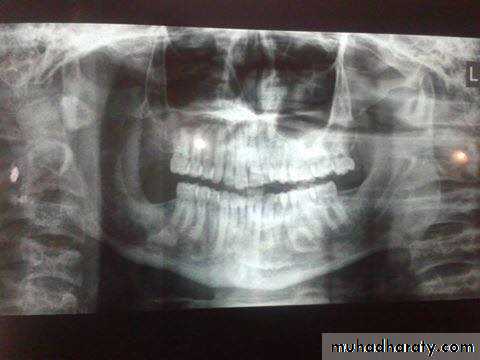

Raioraghical examination may demonstrate unlocular or multilocular types. Unilocular ameloblastomas may be confused with benign cysts. The tumors frequently absorbs the alveolus surrounding ,the roots of teeth and may absorb root ends.